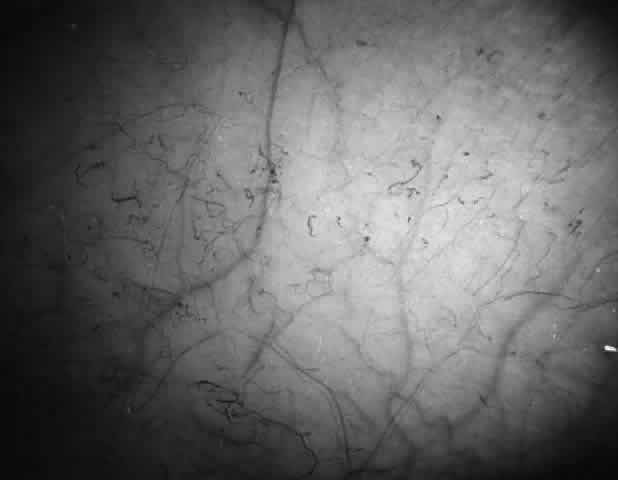

Abnormalities of the bulbar conjunctival blood vessels provide direct evidence of the vaso-occlusive process and were one of the earliest reported ocular changes.38–43 These abnormalities are believed to be the result of flow obstruction or impedance by sickled cells. The severity of the conjunctival changes ranges from linear dilatations to isolated groups of truncated, comma-shaped segments. These changes have been correlated with the ISC count, Hb S concentration, and the intraerythrocytic hemoglobin concentration (Fig. 1).44–47 Although they are known as the conjunctival sickle sign, these vascular abnormalities are not completely pathognomonic of sickle cell disease: in rare cases they are seen in patients with AIDS, chronic myelogenous leukemia, and other vaso-occlusive diseases.47–49

Fig. 1. Conjunctival vascular abnormalities in a patient with homozygous sickle cell anemia demonstrating interrupted, dilated, and truncated vascular segments.